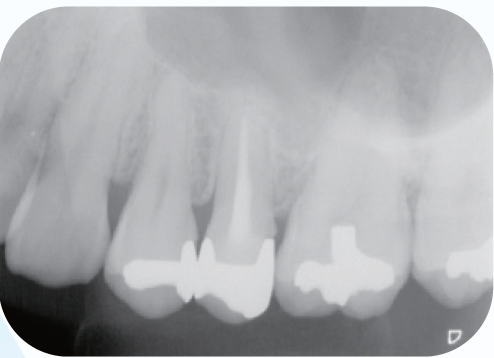

初診時のデンタルX線像を示す。レントゲン所見では根尖周囲組織に炎症を示す像を認め、その影響が上顎洞粘膜の肥厚の原因と推測されるレントゲン像である。

<症例1>●初診時年齢 31歳 女性 初診日2011/10/14

左上5番を他院で根管充填後、打診痛が消失しないので転院され受診患歯にはインレー修復がされている。根尖部は上顎洞と近接しており、上顎洞粘膜の肥厚も認められた

(症例1・①)根管充填の状態は比較的良好である。根管拡大・形成の3次元的評価のためCBCTを撮影。

CT像左上5番根尖部を中心として上顎洞粘膜の肥厚が認められ、根尖性歯周組織炎の影響が上顎洞まで及んでいると考えられた

根管処置後の修復が保存修復されて髄室開拡に制限があり、歯頸部周辺に存在する頬口蓋側に広がる髄角の形態が確認でき(症例1・②)、この部分に根管拡大不足の可能性を疑えた。根尖病変の原因として、頬口蓋的な根管拡大不足による起炎物質の取り残しによる感染が要因の一つであると診断した。より的確な予防形成を行うにあたり、器具操作の向上のため髄室開拡の修正が必要であると判断した。よって最終修復は歯冠修復による補綴修復が必要であると患者に説明し、承諾が得られたので再治療を行なった。

(症例1・②)

線で示した部分に髄角部の形態がそのまま残存していることが予測され拡大不足、未処置部分が存在すると判断した